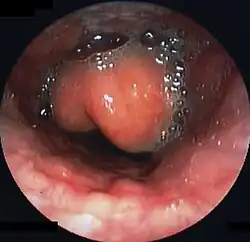

Swollen epiglottis in laryngoscopy

Diagnosis may be confirmed by direct inspection using a laryngoscope, although this may provoke airway spasm.[15] If epiglottitis is suspected, diagnosis is made on basis of fiberoptic laryngoscopy exam carried out in controlled environment like an operating room.[16][17]